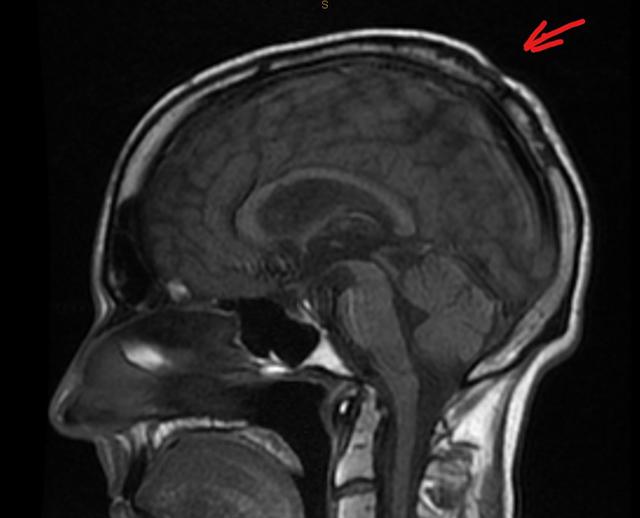

In parting, I came across one of my MRI scans. I can remember what I did to the back of my skull, but it probably hurt.